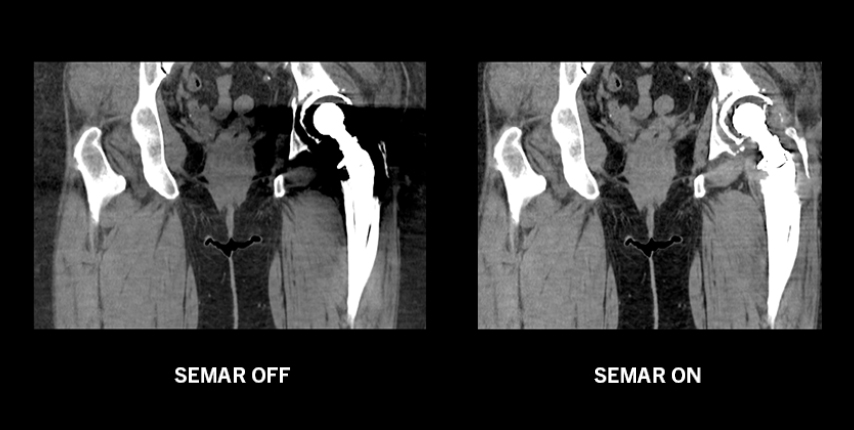

Снижение артефактов металла одной энергии SEMAR

В программе SEMAR (уменьшение артефактов металла одной энергии), разработанной в Canon Medical Systems, используется сложный метод итеративной реконструкции, позволяющий уменьшить металлический артефакт, улучшить визуализацию имплантатов, опорных костей и прилегающих мягких тканей для более четкой и достоверной диагностики. SEMAR может быть установлен в протоколе сканирования, поэтому восстановление полностью автоматическое и не требует дополнительного ввода данных оператором.